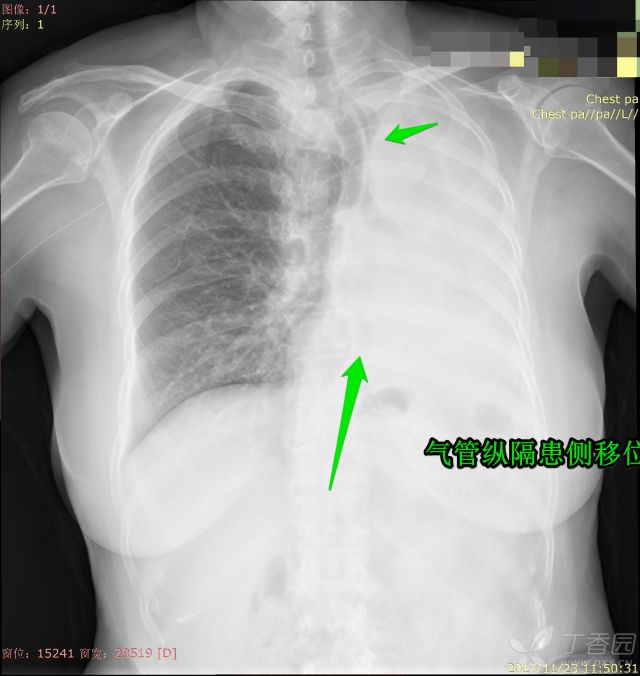

之前我们分享了秒懂胸片!扒一扒胸片的基础知识(可点击查看),那这一次就老生常谈,先发一波病例走起,病例很简单,都是白肺,各位来诊断吧。备选一共有:上叶肺不张、全肺不张、胸腔积液、大叶性肺炎

1.大叶性肺炎

2.胸腔积液

3.全叶肺不张

4.上叶肺不张

这个双侧积液量明显不一样,为何纵隔没有偏移呢?

其实仔细看就会发现萎陷的肺组织,即压迫性肺不张。邻近大量胸腔积液导致肺组织被动塌陷,而这些积液又填充了塌陷肺组织的空间,所以这个纵隔不移位也是很正常的。